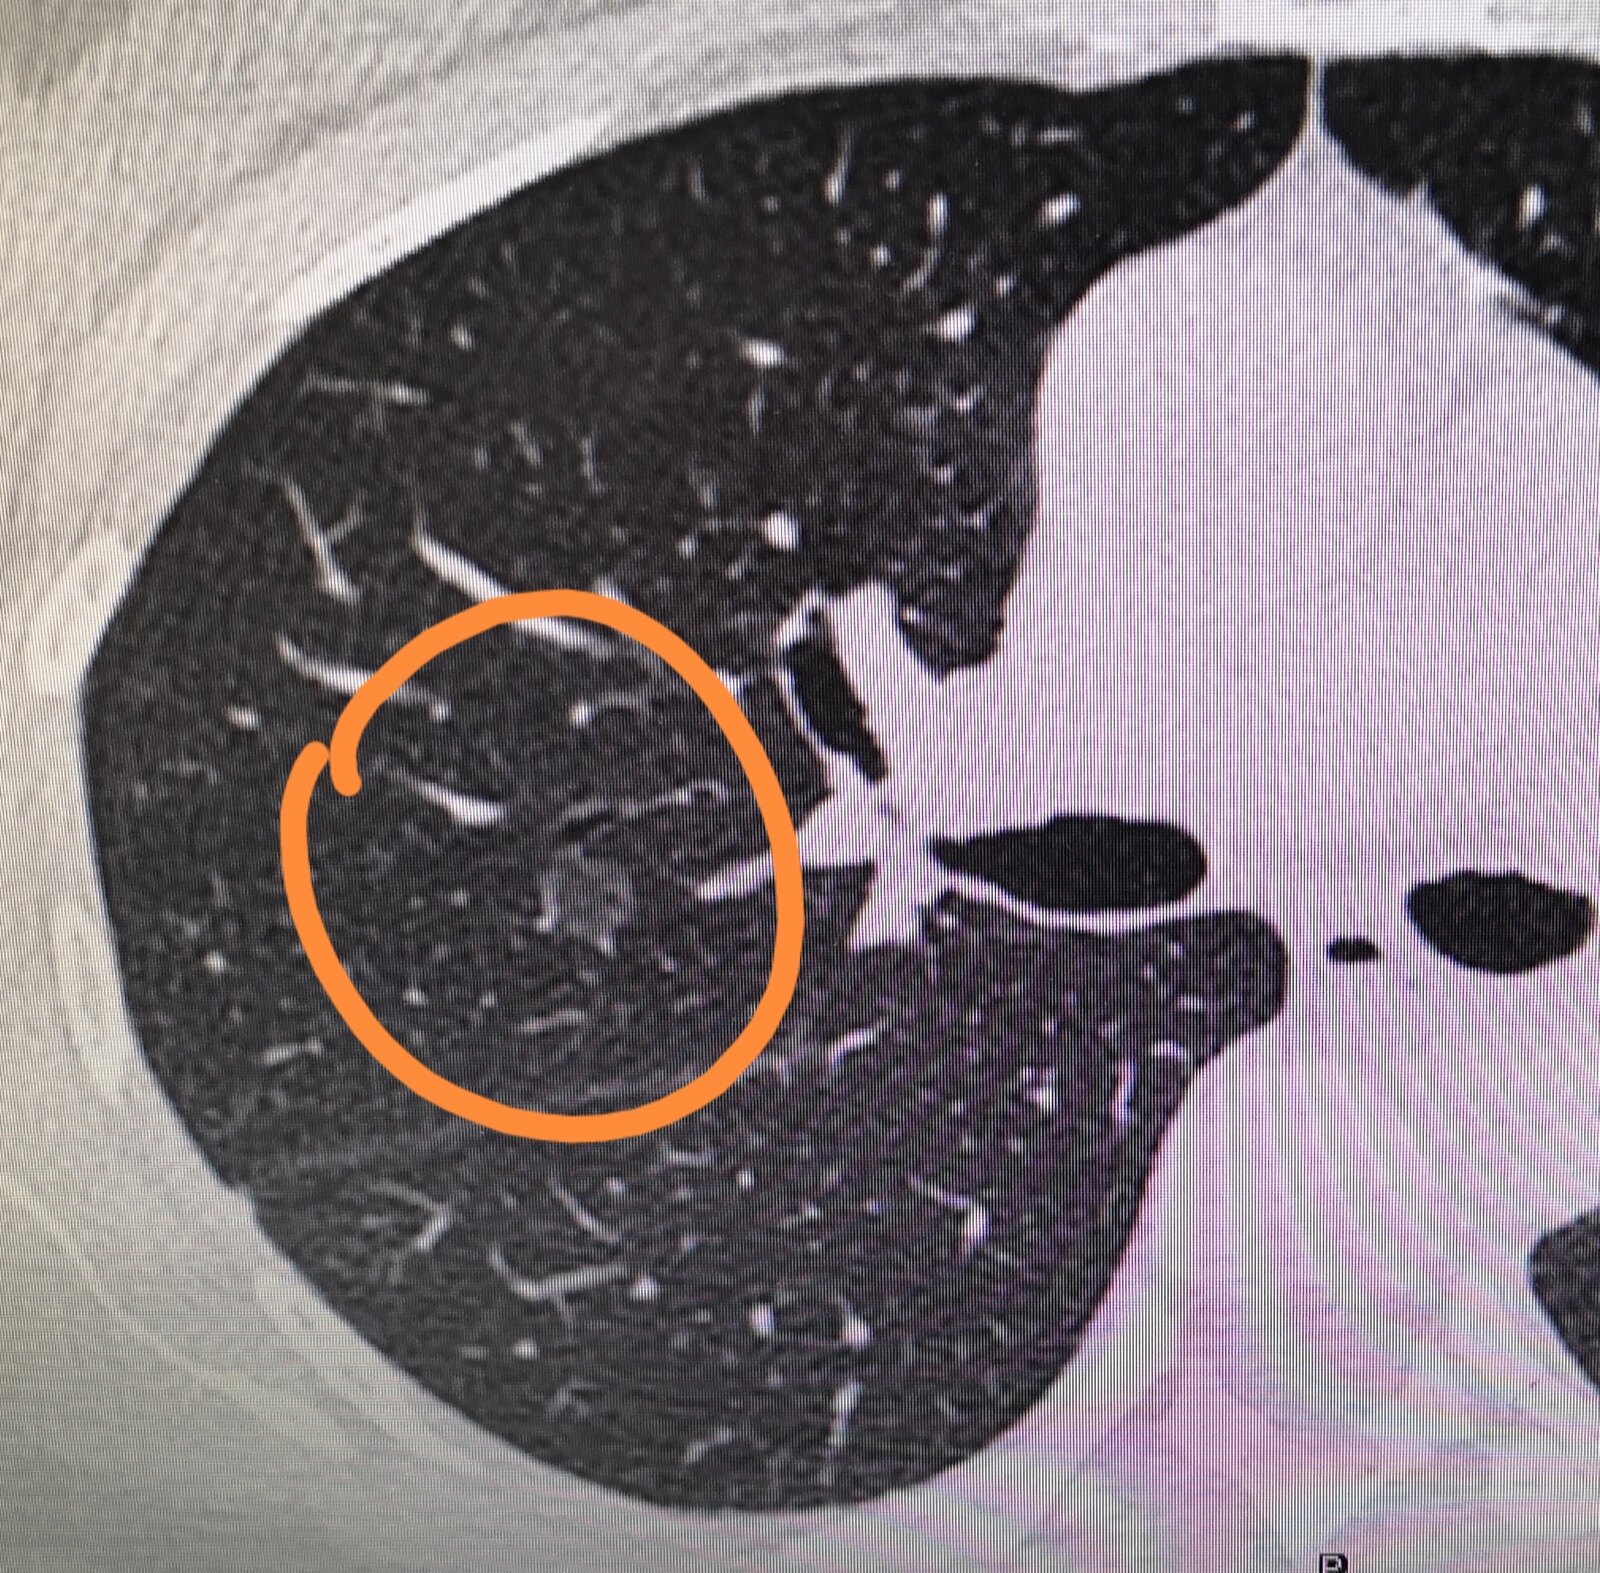

图文教你看懂恶性肺结节的ct表现